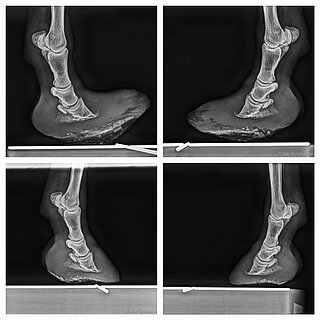

| • | Röntgenuntersuchung | |

| • | Evtl. Hufkorrektur anhand der Röntgenbefunde | |